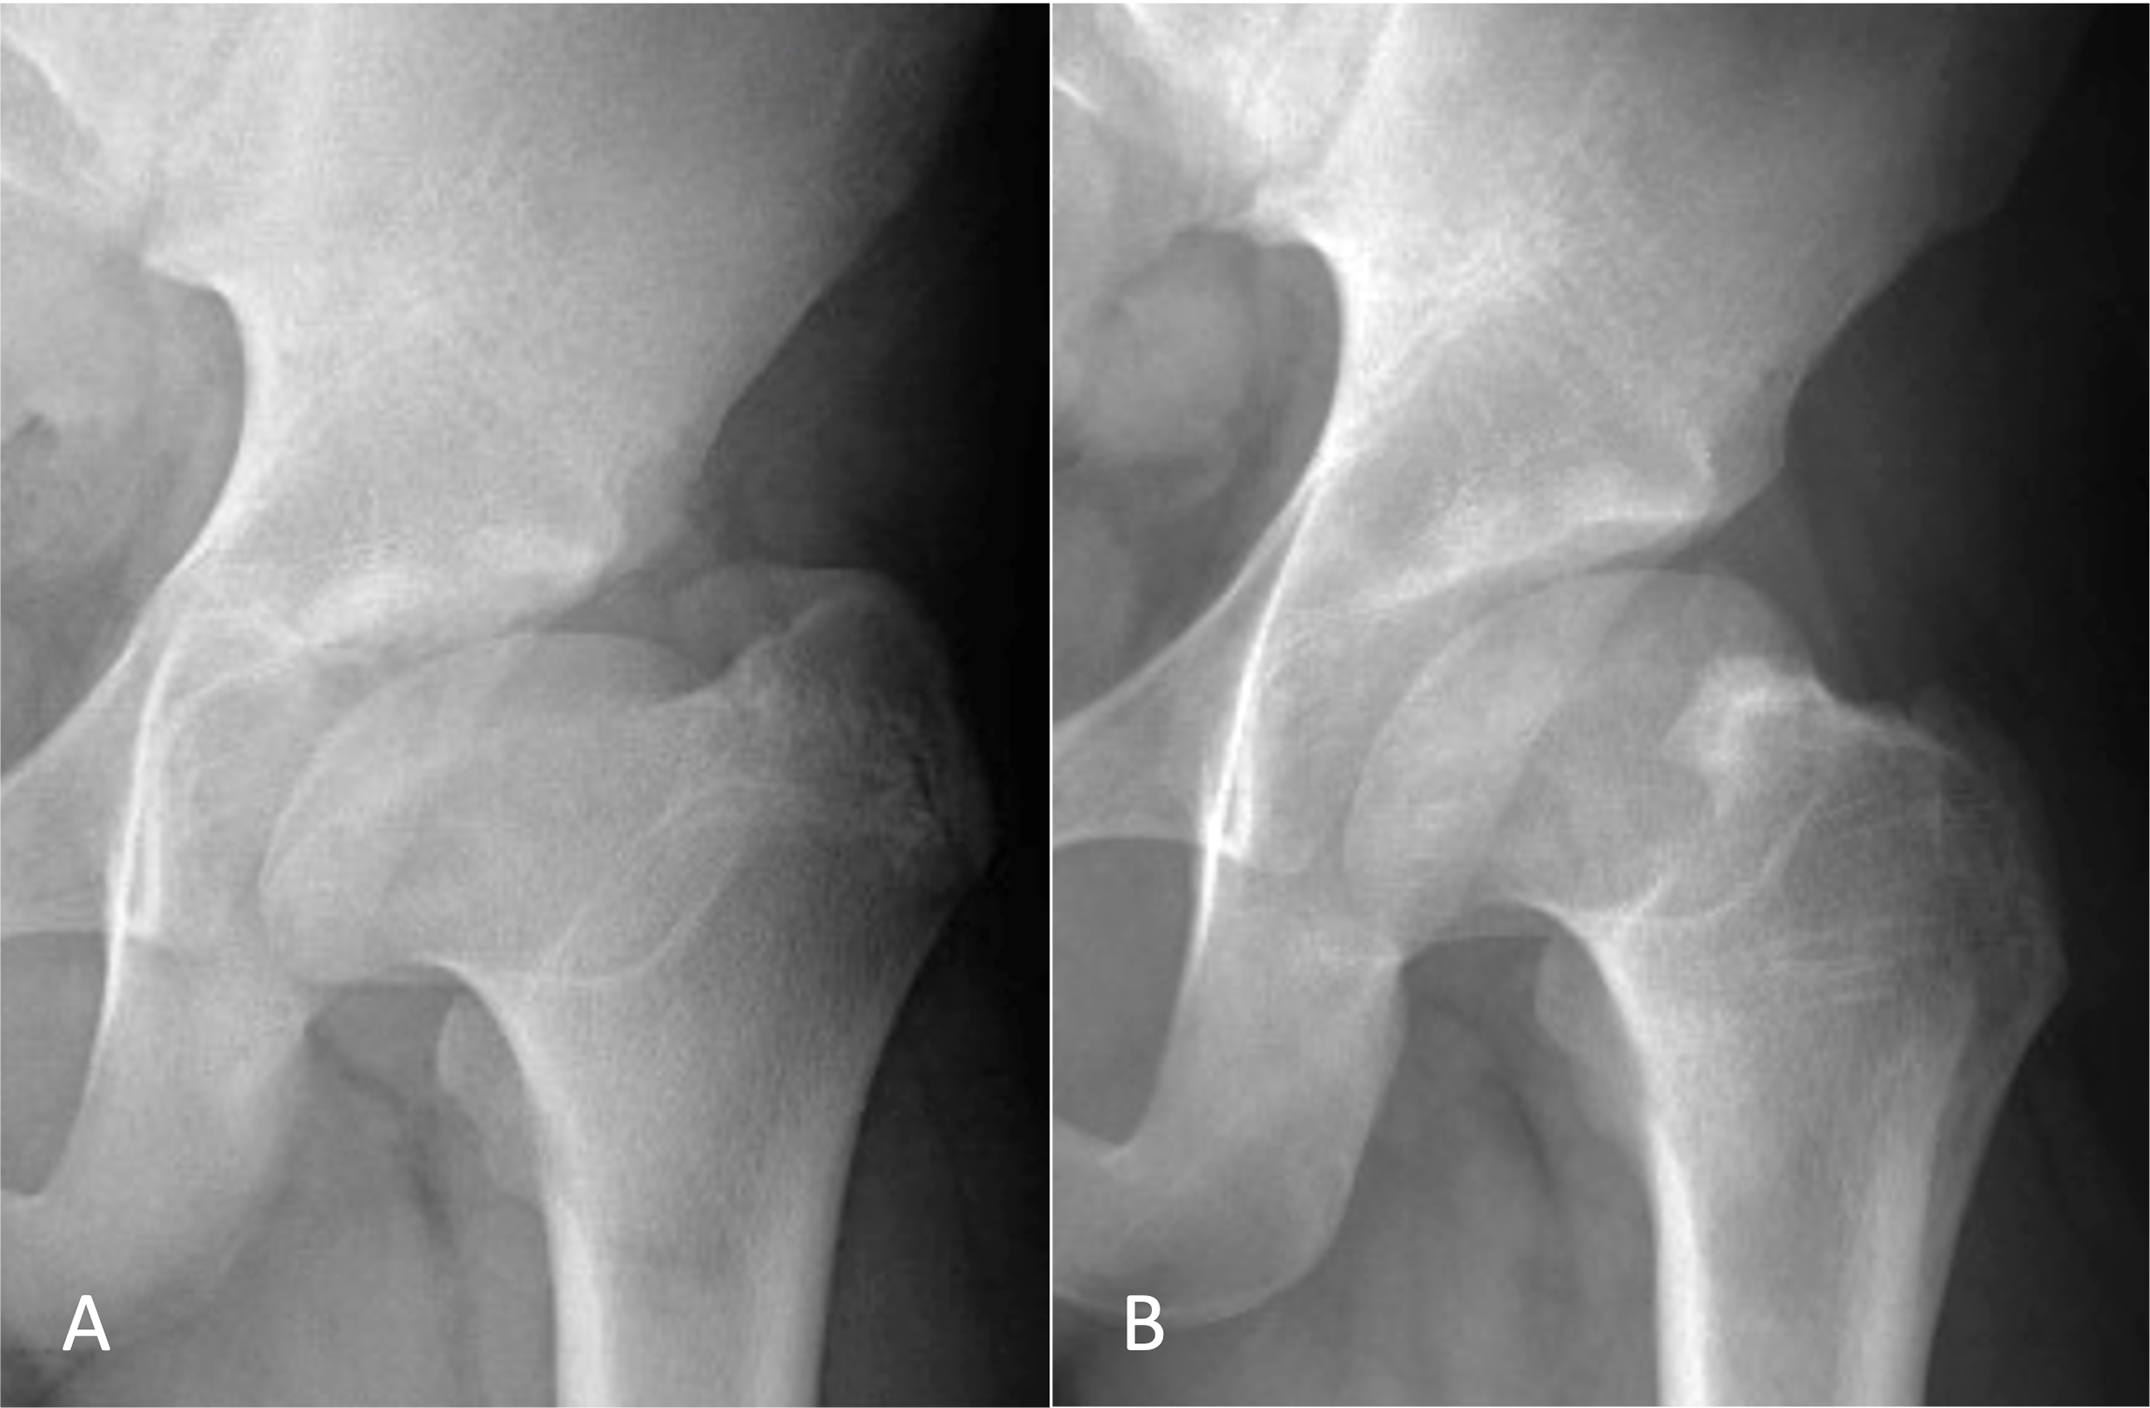

From radiopaedia.org

LeggCalvéPerthes disease Image Is Perthes Disease A Disability In Australia Perthes disease is a condition which affects the hip in growing children. It is more common in boys aged 3 to 11 years old however may develop in girls. Perthes' disease is an uncommon condition that affects children between the ages of three and 11 years. This guide to the list of recognised disabilities is based on determinations approved in. Is Perthes Disease A Disability In Australia.